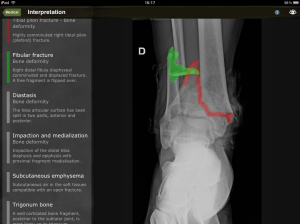

Ahora pasamos a la sección de escaneos, donde tenemos tambien, sus indicaciones, así como la tecnica para realizar el estudio, la anatomía normal, y las distintas patología que podemos diagnosticar usando la ultrasonografía.

Lo único que no me agrado de la aplicación es que, en lugar de tener su contenido en texto, son imágenes de no muy buena calidad, en cuanto al texto me refiero, ya que las imagenes de los ultrasonidos están muy entendibles y con sus respectivas anotaciones.